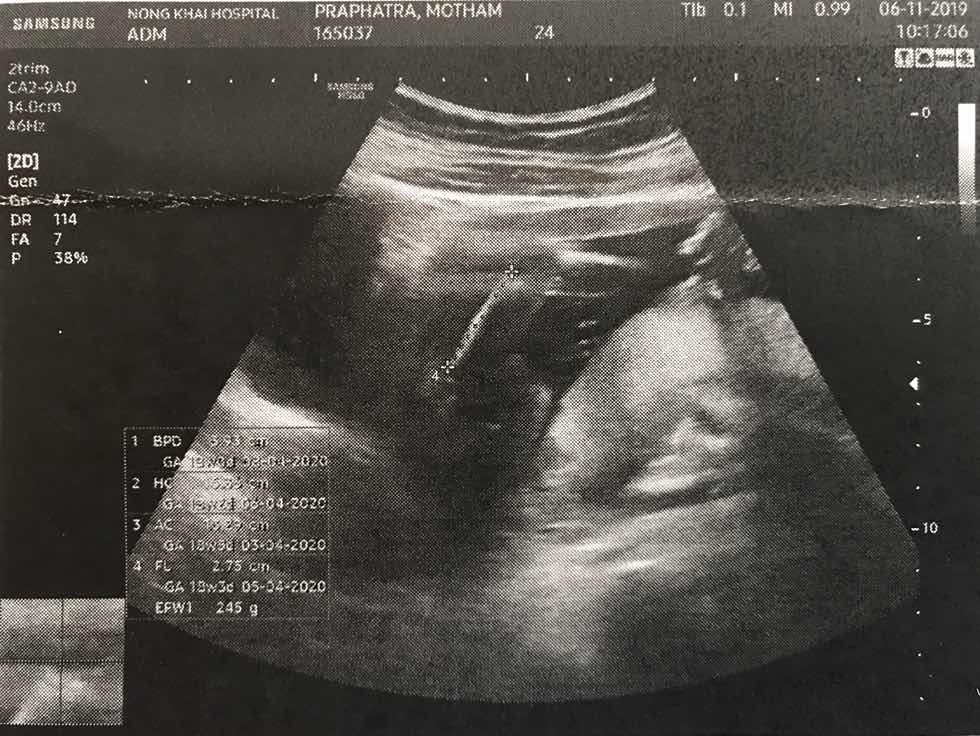

แม่ๆบ้านใหนคลอดเดือนมีนาคมเมษายนบ้างค่ะ ขอดูภาพอัตตราซาวหน่อยจ้าว่าโตแค่ใหนแล้ว